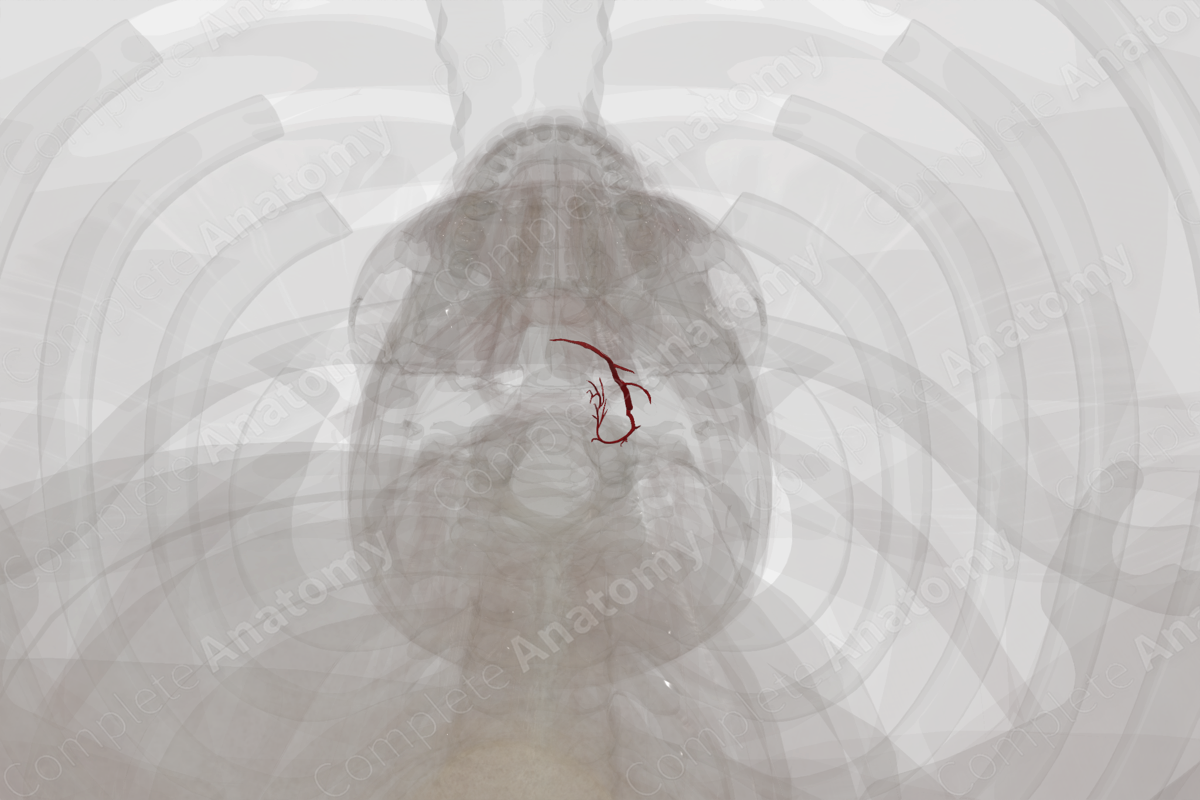

The thyroid gland receives a rich blood supply from branches of the superior and inferior thyroid arteries, and sometimes, by the thyroidea ima artery. These arteries form dense anastomoses on the surface or within the gland.